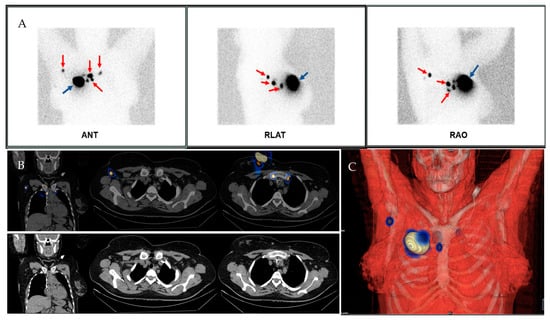

2.1.3. Imaging Acquisition Technique

2.1.4. Intraoperative SLN Identification